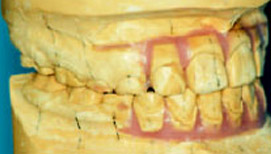

Рис.3:Обратное резцовое перекрытие

Рис.4: Set-up делают только для тех зубов, которые переместить.